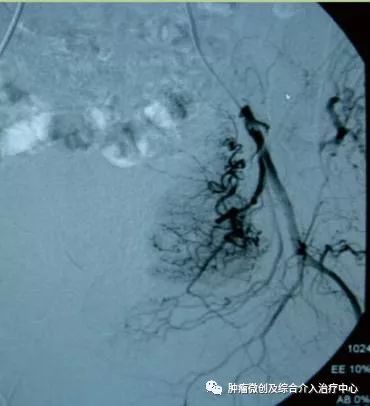

(介入栓塞术后提示无肾动脉出血肾动脉-栓塞成功)